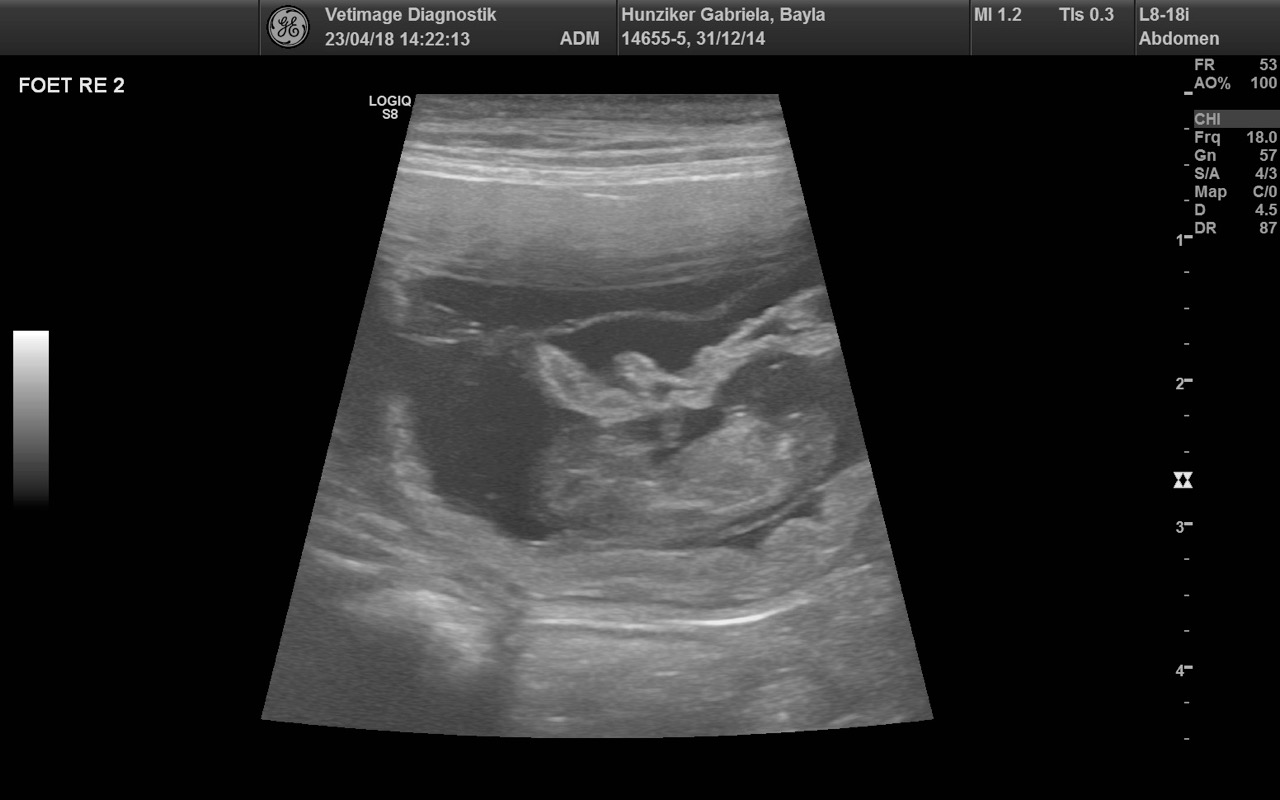

F-Wurf Ultraschall

Wiederum dürfen wir uns freuen... unsere Aileen und Camillo de Manescale werden Eltern.

Diese Verpaarung hat einen speziellen Stellenwert für uns und wir sind sehr gespannt und freuen uns auf die kommenden Wochen.

E-Wurf Ultraschall

Alle Anzeichen deuteten darauf hin... umso schöner ist es, dass wir beim Ultraschalluntersuch vom 23.4.2018 (VETIMAGE in Oberentfelden) die Bestätigung erhielten, dass Joya (Bayla Golden Harmony vom Rebhügel) trächtig ist.